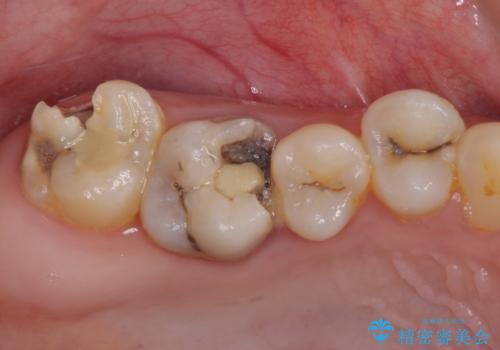

むし歯だらけの奥歯 セラミッククラウンによるむし歯治療

- 奥歯のむし歯を気にして来院された患者様です。

痛みのある歯が多く、根管治療が必要と診断されました。

左下の歯は、クラウンを装着するために必要な高さが足りないため、歯冠長を延長するための外科処置を行うこととしました。

根管治療や歯周外科処置後にフルジルコニアクラウンにて補綴治療することとしました。

自身の口腔内への意識が高くなく、汚れが非常に多い方でした。